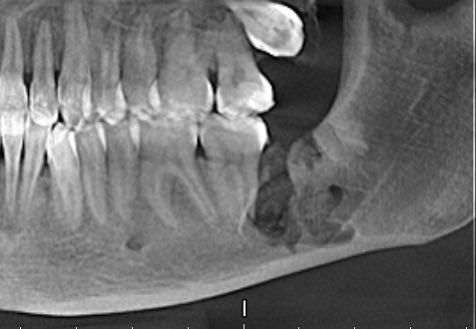

Я работаю в одном из московских стоматологических институтов и иногда приходят пациенты с зубами мудрости, от которых у меня впоследствии дергается глаз.

Например тут зуб мудрости располагался на самом нижнем углу челюсти и был полностью спаян с лицевым нервом.

Спустя час зуб я удалил, отделил от нерва, а чувствительность у пациента спустя неделю почти полностью восстановилась.